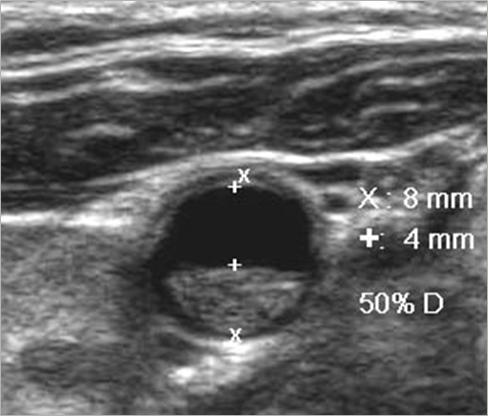

What is the diameter of the CCA?

5-6 mm

What is the diameter of the ICA?

4-5 mm

What is the diameter of the ECA?

3-4 mm

How should plaque be measured?

transverse measurement

lumen vs true lumen

Why is plaque measured in transverse?

Longitudinal estimation of stenosis from B-mode image is usually unreliable, use transverse image.

*This minor plaque can be made to appear more or less stenotic in longitudinal view